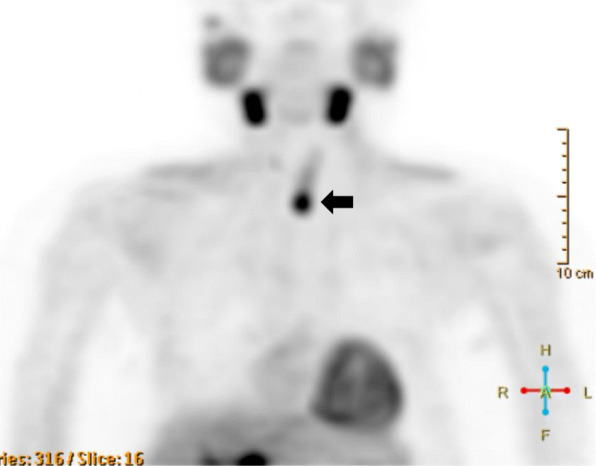

Fig. 5.

11C-methionine PET-CT findings after the removal of the upper and lower parathyroid glands. Methionine-positive tumor right next to the trachea (arrow)